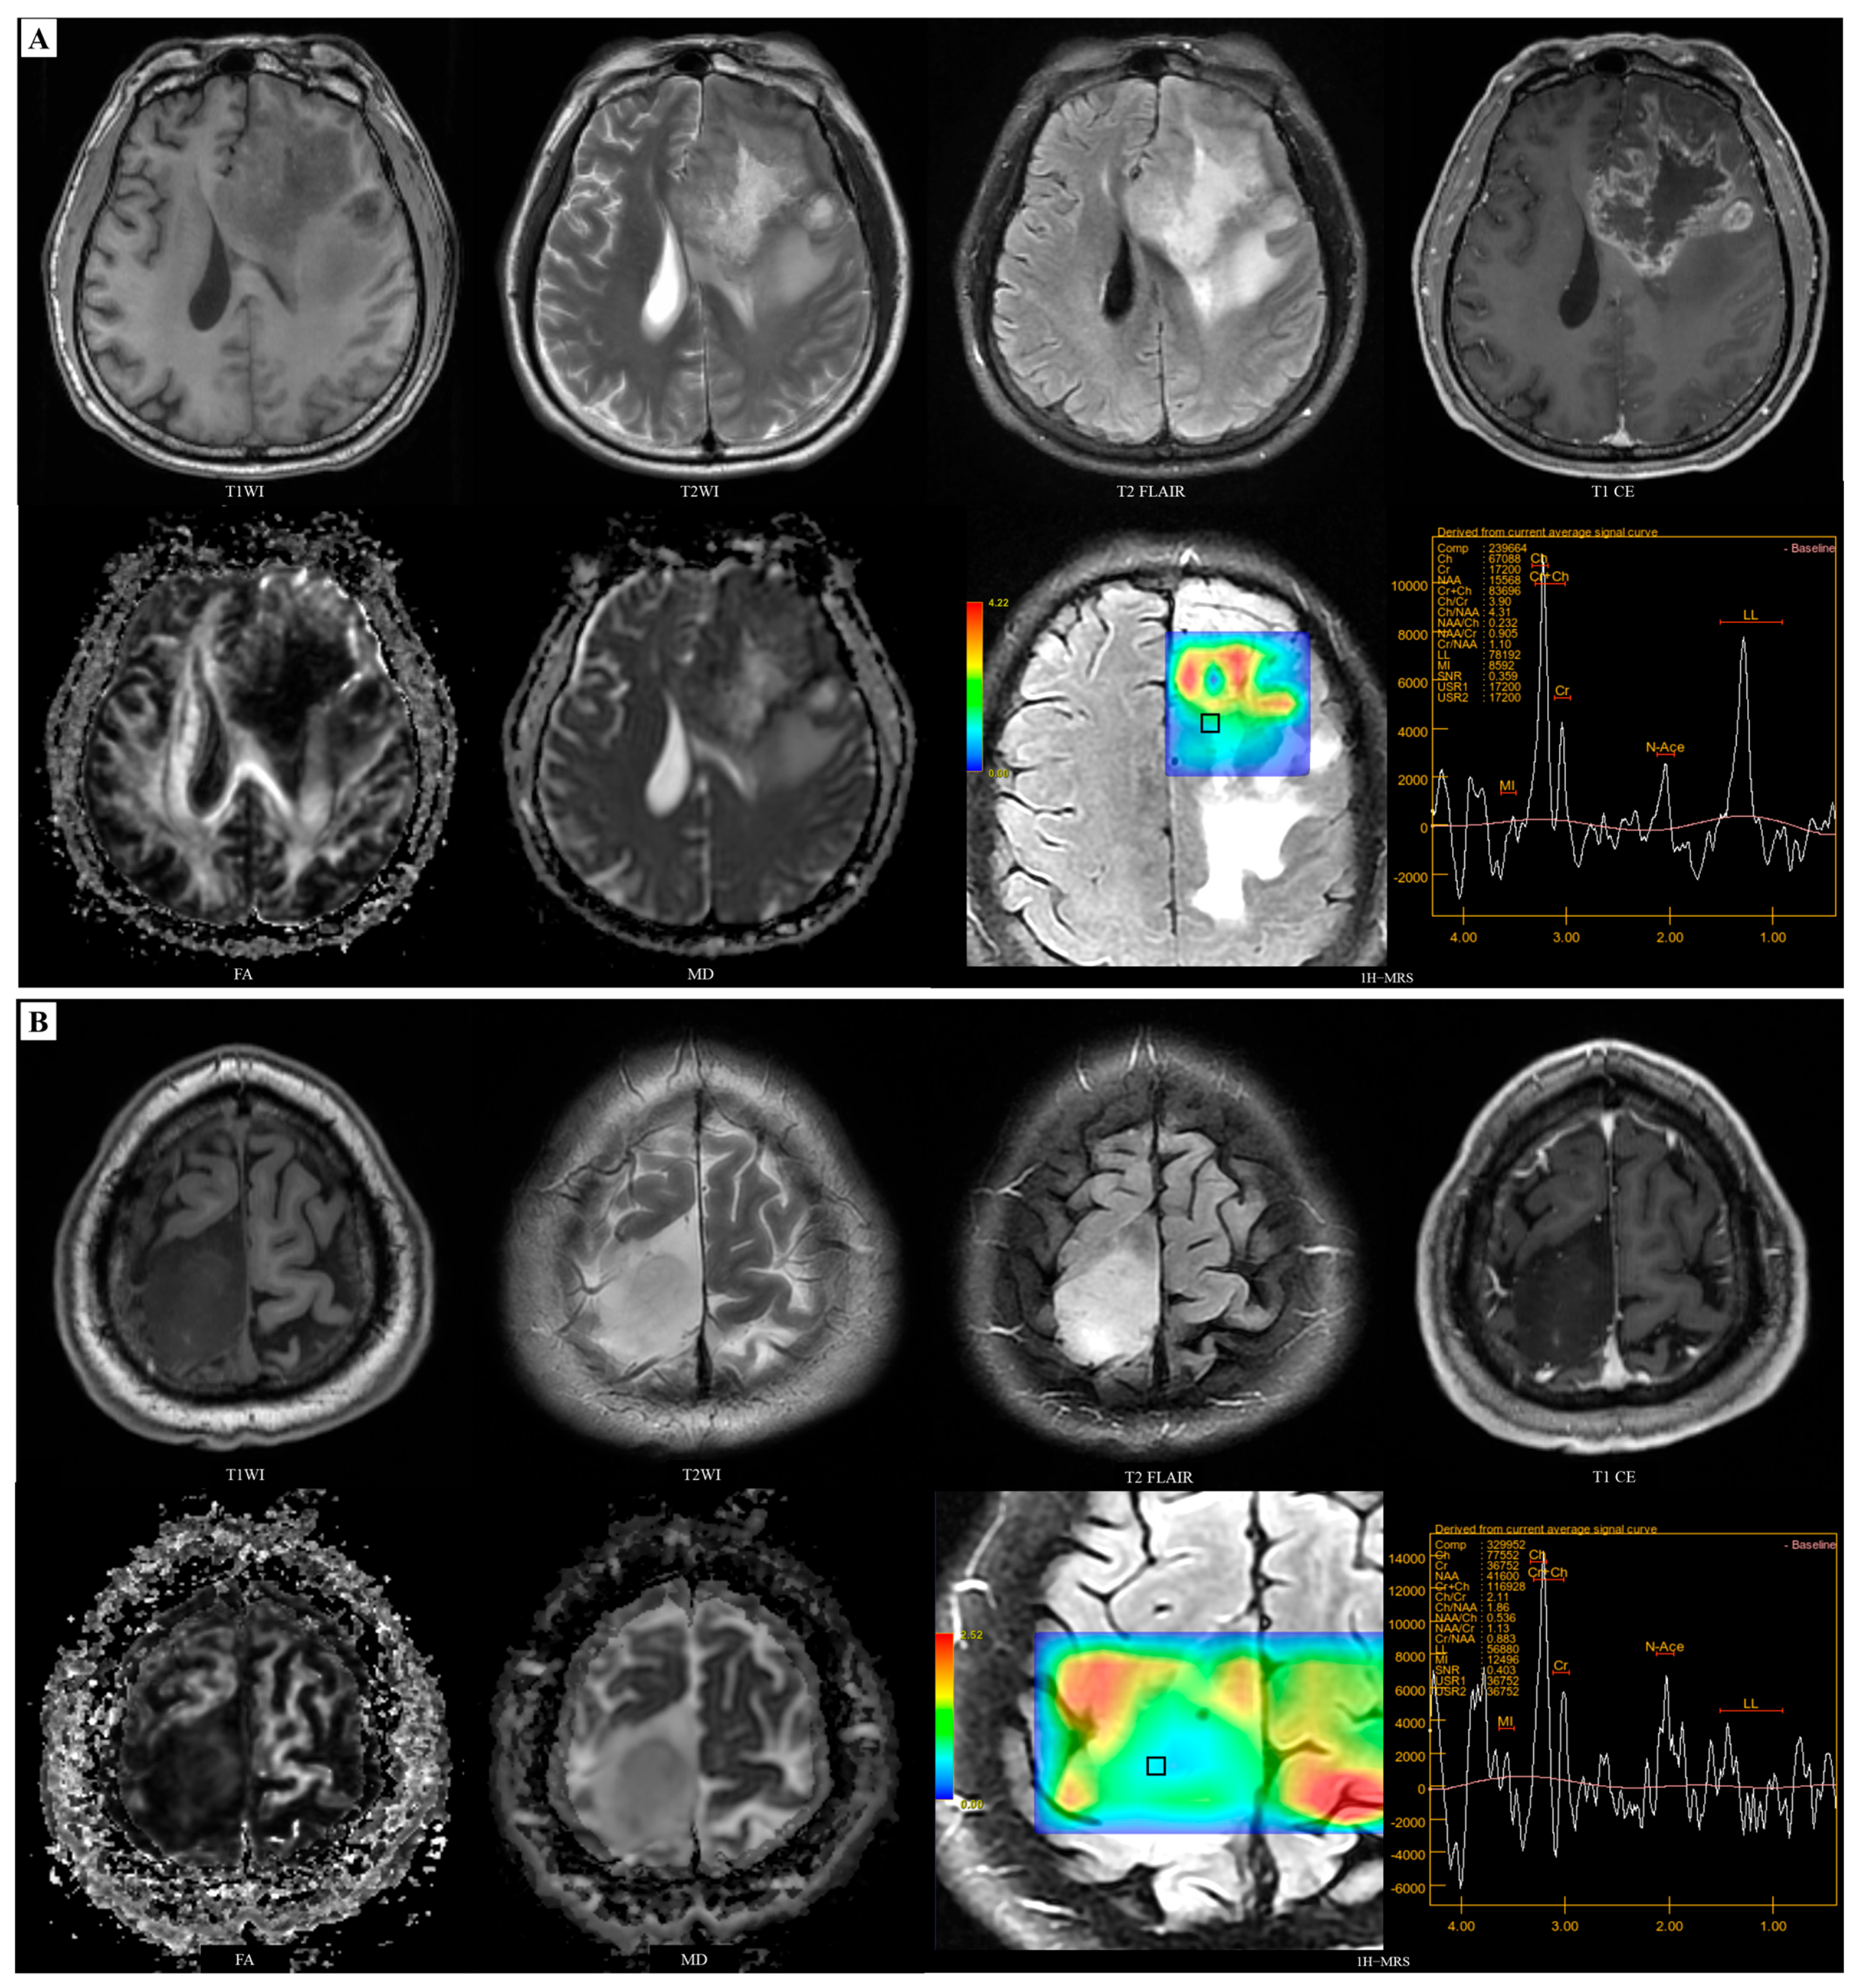

2.3. Imaging Analysis